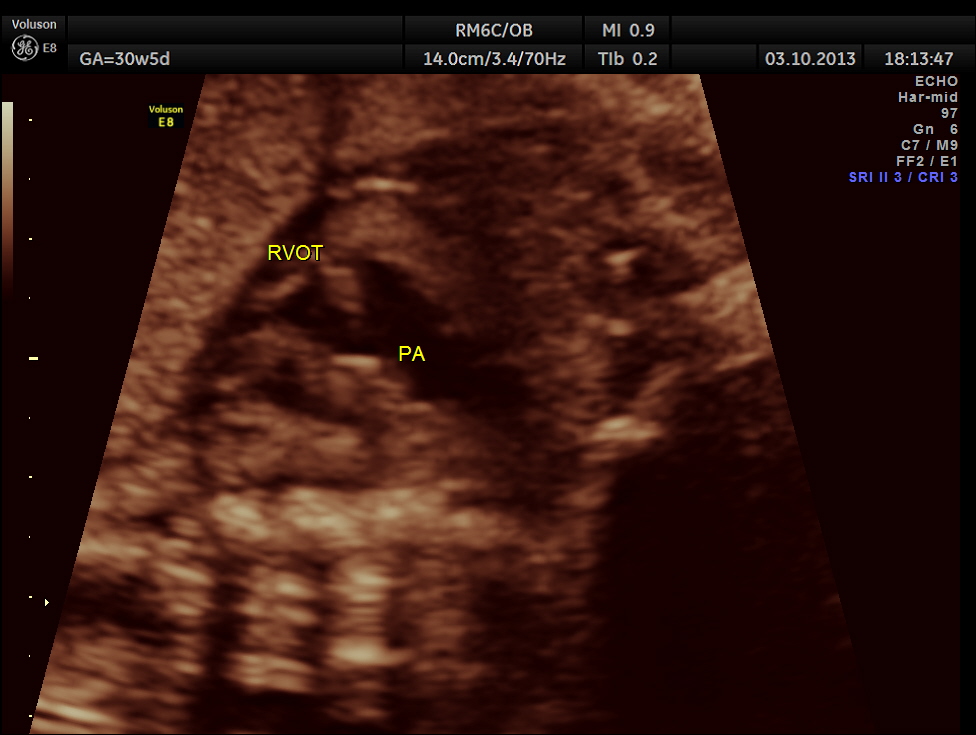

The following pictures belong to two scans done at 31 weeks of gestation.

The rest of the scan appeared normal.